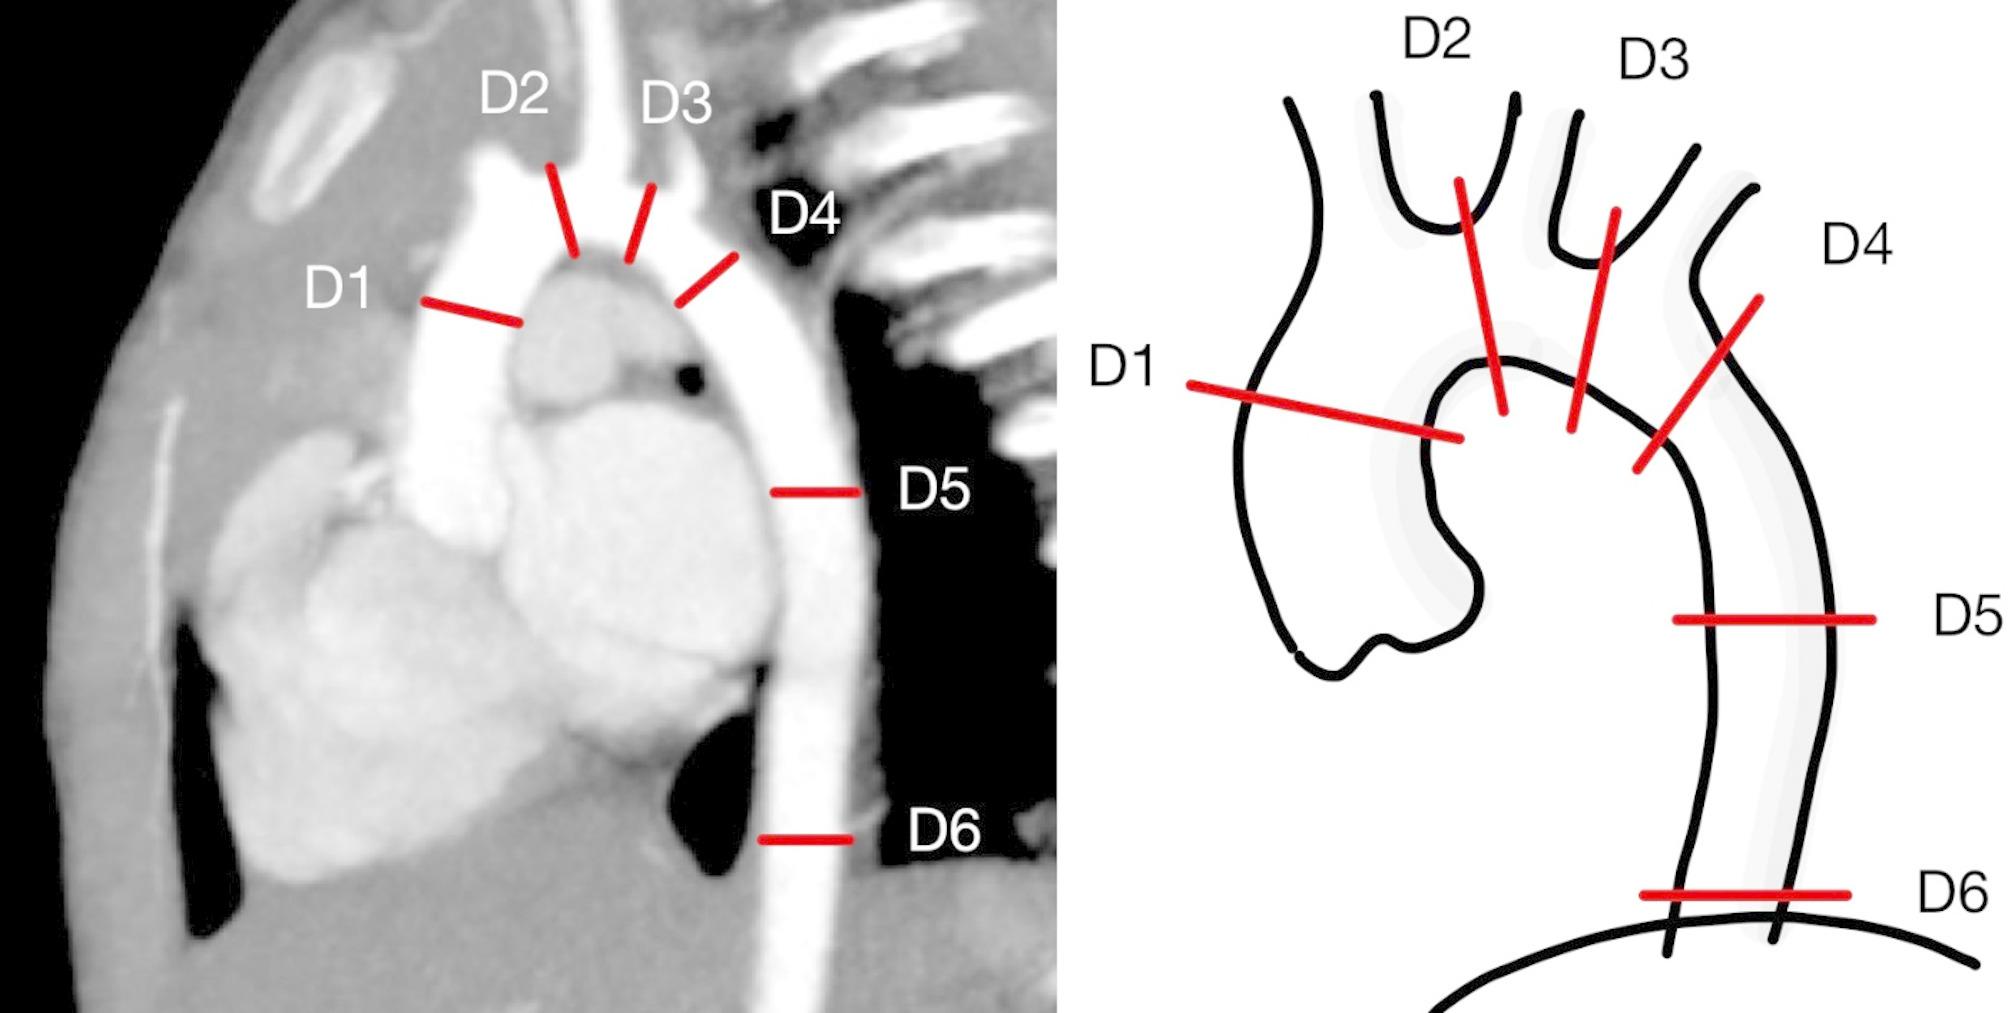

Methods: Patients who underwent aortic anastomosis for symptomatic coarctation during their first year of life between 2008 and 2023 and were still alive were included in the study for evaluation. Aortic arch diameters were assessed using computed tomography angiography (CTA), and z-scores were calculated. For patients with recurrent stenosis who required subsequent surgery, the surgical pathology was reviewed.

Results: A total of 15 patients underwent CTA assessment, with a median time from surgery to CTA of 8.08 years (4.39, 10.02). The z-scores for the diameters at the repaired areas were as follows: for the distal transverse arch, the median z-score was - 0.08 (-0.52, 0.59), and for the descending aorta at the anastomosis, it was 1.13 (0.18, 1.72). When comparing the two subgroups-7 patients with aortic arch hypoplasia and 8 without-no significant differences were found in the z-scores of the diameters at the repaired sites. In one case of restenosis at the 4-year follow-up, subsequent surgery revealed that the suture line did not align with the narrowest segment.